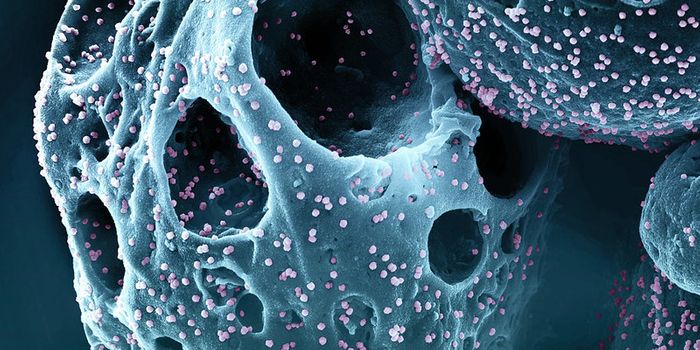

MAR 15, 2020MicrobiologyNew research has suggested that after long-term follow-up, HIV is no longer detectable in a patient that was previously ...

JUL 11, 2021MicrobiologyIn October 2020, what's now called the Delta variant of SARS-CoV-2 was first detected. It's now the most prevalent strai ...

SEP 20, 2021Genetics & GenomicsHuman immunodeficiency virus (HIV) is a retrovirus, which is a type of virus that can write its genetic material into th ...